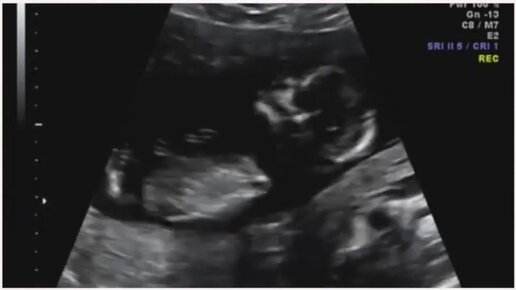

УЗИ на 13 неделе беременности

Медицинский женский центр